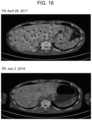

FIG.10 includes a graph (A) showing the levels of cancer inflammation markers (white blood cell count, neutrophil count, CRP) in the blood, the level of immunity improvement markers (lymphocyte count) and N/L ratio measured with time after a gastrointestinal medicine containing Taxotere and sodium hydrogen carbonate were administered to a female patient (45 years old) diagnosed with breast cancer; and photographs showing chest CT images (B). The white arrows indicate tumors (B).

FIG.11 includes chest X-ray photographs (A) of a female patient (54 years old) diagnosed with recurrent breast cancer before and after administration of tamoxifen and intake of sodium hydrogen carbonate and a plum extract; and a graph (B) showing the levels of tumor markers (BCA225, CA15-3 and CEA) in the blood measured with time.